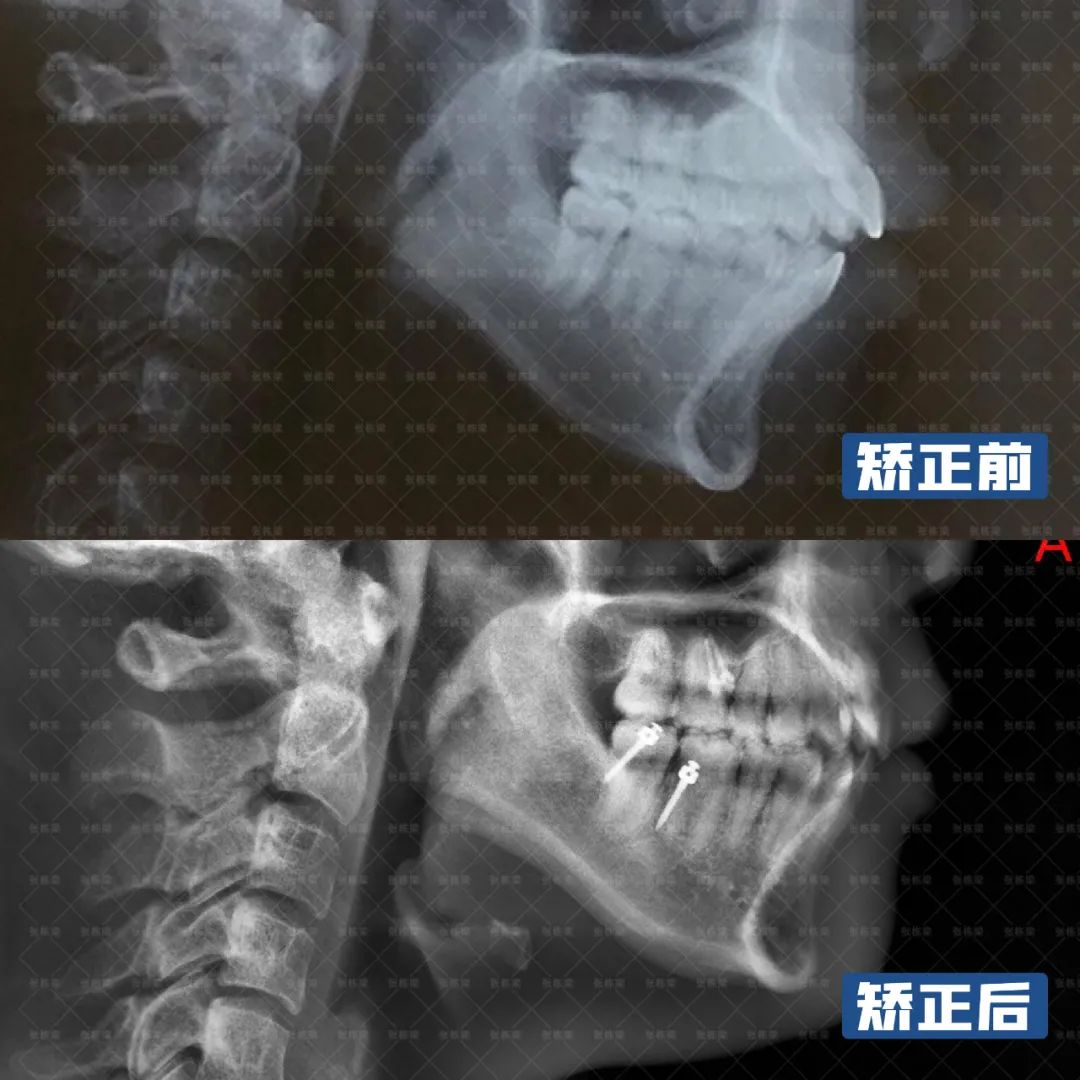

这位女士主诉开颌,下巴后缩,综合牙片面型检查,骨性II类倾向、前牙3-3开颌,上下牙唇倾,下巴后缩。

由于开颌通常伴随下巴后缩,也因此伴随着下颌髁状突吸收,而且两者相互影响,互为病因,因此逆时针旋转下颌是牙齿矫正开颌问题的主要目标。

牙齿矫正结束后,从牙齿上看,上下前牙牙转矩角度正常,前后牙距离关系恢复正常,尖窝关系良好,上下牙弓也恢复协调。

从面型上看,下巴前伸,颏肌放松了,面部肌肉轮廓协调、放松,加上女士本身是高角长脸面型,下巴逆旋后,可以让面部高度比例更加协调。